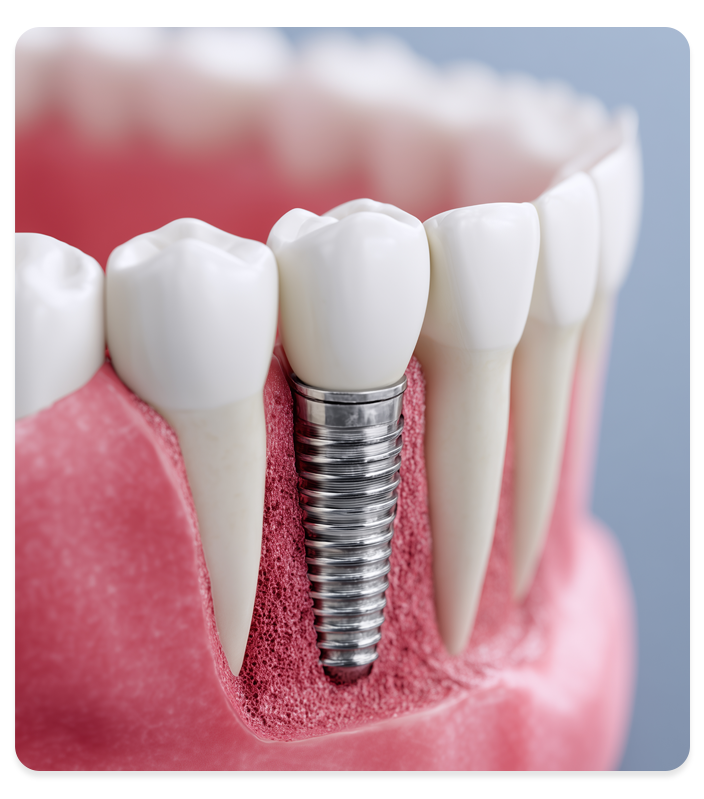

임플란트 식립

정밀한 각도와 깊이로 안전한 식립